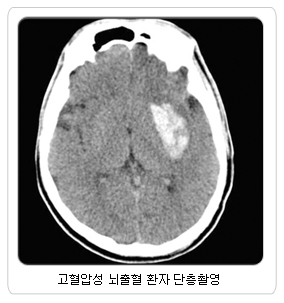

고혈압성 뇌출혈은 혈압조절로 예방하는 것이 가장 중요 우리 인체 중 뇌는 1.2kg 밖에 되지 않으나 전체 혈액량의 1/4을 사용하는 혈관이 매우 풍부한 조직입니다. 풍부한 혈관에 문제가 발생하여 혈류의 이상이 발생된 경우를 뇌졸중이라 합니다. 뇌졸중은 뇌혈관이 막혀 뇌경색증이 발생하거나 혹은 뇌혈관이 터져 뇌출혈이 발생되는 병이고 과거엔 중풍이라고 불리던 병입니다. 이렇게 터지거나 막히는 반대되는 개념의 질환을 모두 뇌졸중이라 부르는 이유는 증상이 유사하기 때문입니다. 증상으로는 병변 부위에 따른 다양한 신경학적 증상부터 언어장애, 반신마비, 심지어는 사망에 이를 수 있는 다양한 증상을 나타냅니다. 그러면 뇌졸중의 대표질환인 고혈압성 뇌출혈, 뇌동맥류 파열, 뇌경색증에 대하여 알아보겠습니다. 고혈압성 뇌출혈의 위험인자로는 고령, 고혈압, 뇌경색의 병력, 심장의 관상동맥 질환, 당뇨병 등이 있습니다. 이 중 가장 중요한 원인은 만성 고혈압으로 혈압 상승의 정도와 기간에 관련이 있습니다. 즉 고혈압 수치가 높거나 고혈압의 기간이 길수록 많이 발생합니다. 고혈압성 뇌출혈이 발생되는 동맥은 직경이 큰 뇌동맥이 아니라 대부분 크기가 작은 관통동맥에서 발생합니다. 관통동맥은 분지가 되지 않아 단계적인 압력의 감소가 일어나지 않으므로 혈관 내압이 높고 고혈압에 의한 혈관 손상에 취약하므로 이 부위에서 고혈압성 뇌출혈이 발생하게 됩니다. 고혈압성 뇌출혈이 발생된 환자는 병원에서 뇌수술을 포함한 다양한 방법으로 치료하게 되지만 많은 환자에서 뇌출혈의 후유증으로 본인과 가족이 고통 받게 됩니다. 그러므로 고혈압성 뇌출혈은 혈압조절로 예방하는 것이 가장 중요하다 하겠습니다.